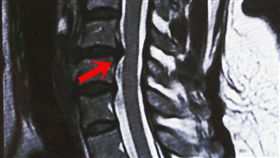

手舉不起來 竟是17年前腎癌骨轉移

「肩膀痠痛」是中老年族群常見的困擾,多數人經過休息或...